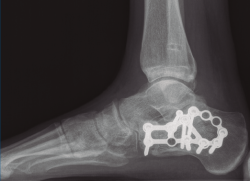

Se dio de alta el día siguiente a la cirugía con un buen control analgésico. En la radiografía de control postoperatoria presentó una correcta reducción tanto de la fractura de calcáneo como de la articulación tibioperoneo astragalina (Figuras 9 y 10). Se citó en consultas externas 2 semanas después para la retirada de la sutura, presentado un buen aspecto las heridas quirúrgicas (Figura 11), y para la colocación de un botín de yeso. Dicho botín fue retirado al mes y medio de la cirugía, colocándose una ortesis estabilizadora de tipo Walker y autorizándose la carga parcial y progresiva, comenzando la rehabilitación.

A los 9 meses únicamente presentó dolor ocasional al nivel de la articulación subastragalina y molestias en la planta del pie al deambular descalzo, por lo que se pauta plantilla amortiguadora, con la que mejora notablemente la sintomatología. Presentó una puntuación de 83 sobre 100 en la escala de la American Orthopaedic Foot and Ankle Society (AOFAS), ligeramente superior a la media descrita en estudios previos(2,3). Radiográficamente se evidenció una anatomía restablecida del calcáneo y de la sindesmosis, así como una altura adecuada de ambos tobillos (Figuras 12 y 13). Dada la buena evolución, se decidió continuar con el seguimiento anual del paciente sin realizar la extracción del material de osteosíntesis, para valorar la necesidad de una futura artrodesis sub­astragalina.

Figura 12. Radiografía de perfil a los 9 meses de la cirugía.